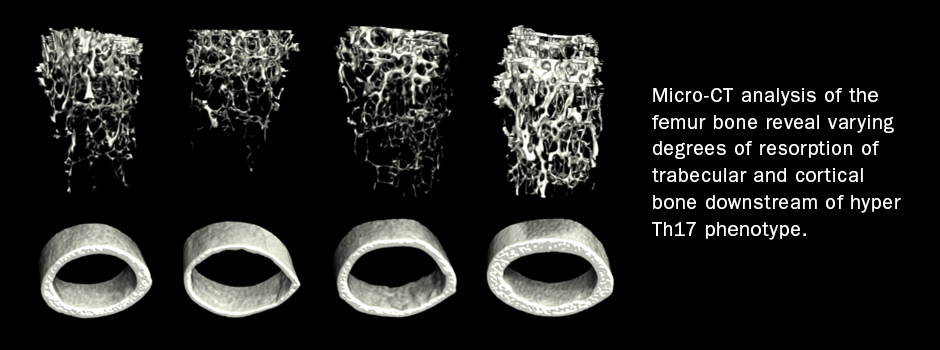

We are leveraging of our expertise in conditional gene targeting, cutting edge multimodal single-cell sequencing, and our great relationship with clinical collaborators to pursue projects related to both basic immunology (B and T cell development) and clinically relevant questions in infection, autoimmunity and cancer.